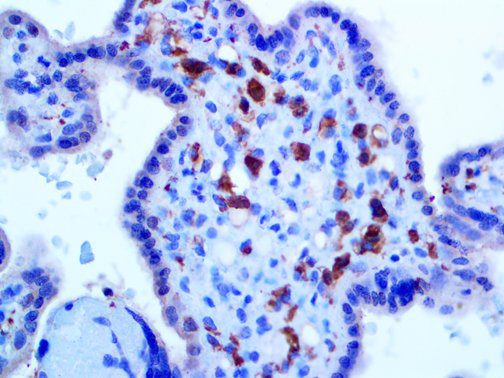

It is the ICU physician who is most likely to witness one of the deadliest manifestations of the abnormal immunological response, the cytokine storm syndrome (CSS). This response is also referred to by some as the cytokine release syndrome (CRS). CSS is characterized by continuous activation and expansion of macrophage and lymphocyte populations, which secrete large amounts of cytokines, causing the cytokine storm. This massive cytokine release is akin to hemophagocytic lymphohistiocytosis (HLH) disease, a syndrome characterized by initial unchecked and persistent activation of cytotoxic T lymphocytes and NK cells.

Clinical and laboratory manifestations of HLH include fever, enlarged liver and/or spleen, neurologic dysfunction, coagulopathy, liver dysfunction, cytopenias (i.e., low levels of erythrocytes, leukocytes, and/or platelets), hypertriglyceridemia, hyperferritinemia, hemophagocytosis, and eventually diminished NK cell activity as the immune system becomes progressively paralyzed. HLH can be familial (primary HLH) or secondary to another disease process (sHLH), such as rheumatic disease, in which it is referred to as macrophage activation syndrome (MAS, characterized by elevated ferritin).